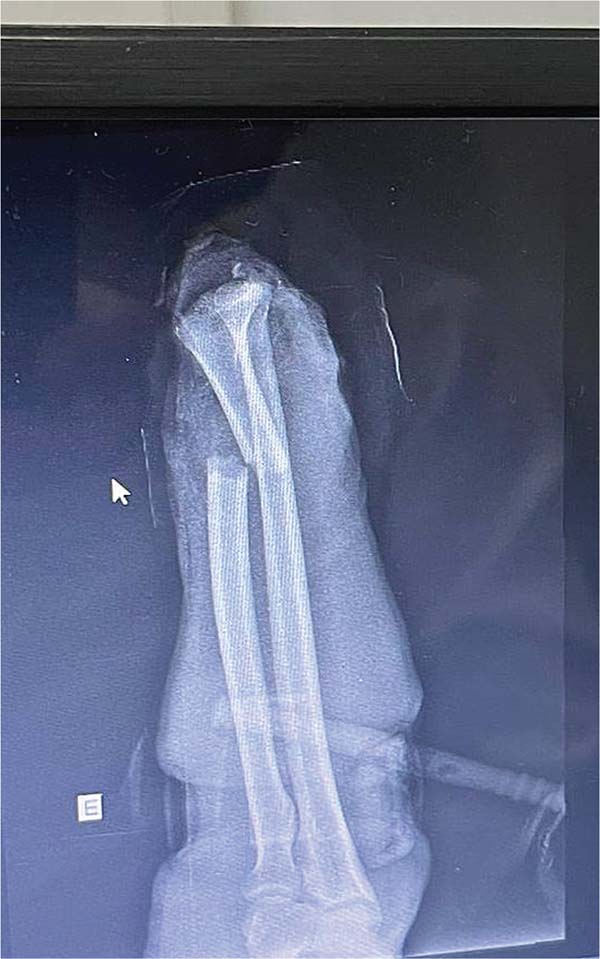

Um paciente (IPB) de 56 anos, do sexo masculino, casado, natural e procedente de Fortaleza, deu entrada no hospital decorrente de acidente por serra em ambiente de açougue. Ele apresentava amputação total da mão esquerda ao nível de punho com exposição óssea e tendínea, com torniquete no esquerdo e mão acondicionada em recipiente com gelo. Relatou que o acidente ocorreu há aproximadamente 40 minutos. Ao exame apresentava-se estável, porém moderadamente hipocorado devido a perda sanguínea significativa, porém sem perda de consciência com frequência cardíaca próximo a 110 bpm se enquadrando em choque hipovolêmico grau 2. Não havia sinais de escoriações ou trauma em outros membros (►Figs. 1-3).

Fig. 1 - Mão amputada.

Fig. 2 - Coto proximal do antebraço.

Fig. 3 - Radiografia pré-operatória.